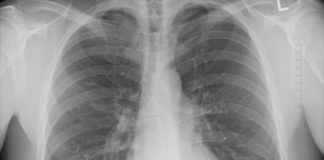

Tag: lung cancer screening

Lung cancer is the nation's leading cause of cancer deaths, and this year 850 Utah residents will be diagnosed with the disease....